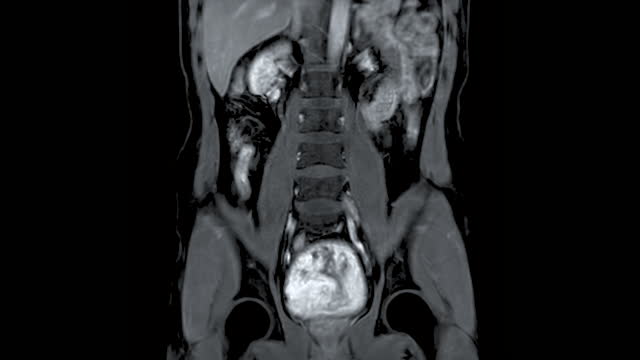

신장암은 혈액 검사나 소변 검사로는 조기 진단하기 어렵습니다. 따라서 건강을 유지하고자 하는 목적으로는 초음파 검사를 적어도 일 년에 한 번 받는 것이 좋습니다. 초음파 검사를 통해 작은 크기의 신장암도 조기에 발견할 수 있습니다.

현미경적 혈뇨는 신장암의 초기 증상 중 하나로 나타날 수 있습니다. 이는 소변에서 피가 혼합되어 나오는 것을 의미합니다. 때로는 눈에 띄지 않을 수 있지만 검사를 통해 혈뇨가 확인될 수 있습니다. 특히 50세 이상의 연령대에서 현미경적 혈뇨가 나타날 경우, 초음파 검사나 CT 검사와 같은 특수 검사를 받아야 합니다. 이를 통해 신장암의 가능성을 조기에 확인할 수 있습니다.